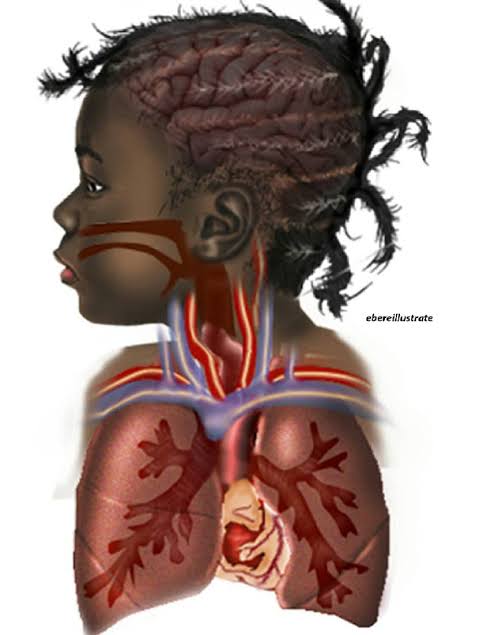

The image of a black fetus inside a black woman’s womb; which was illustrated by Chidiebere Ibe and posted on 24th November 2021; went viral and also opened up conversations regarding the underrepresentation of black people in medical illustrations. On Twitter, the image was liked over 8,000 times and retweeted over 2,500 times. Also, On Instagram, the image was liked over 100,000 times. One twitter user shared the photo and wrote, “I’ve literally never seen a black fetus illustrated, ever.” And now, for his noble efforts; the young medical student and aspiring neurosurgeon is set to have his illustrations published.

Despite making up an eighth of the world’s population, Africa accounted for less than 1% of global research output between 2012 and 2016. Even in Nigeria, White skin images dominate the medical literature, says Ibe. His goal is to help remedy that by setting up a network of African medical illustrators.

Ibe plans to become a pediatric neurosurgeon and is also working on a textbook on birth defects in children; which will be illustrated with Black skin images.